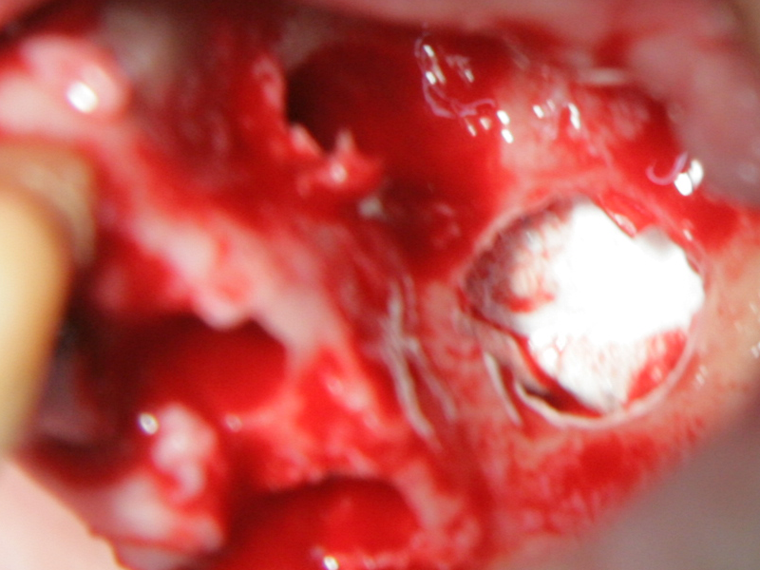

Отворен максиларен синус в началото на интервенцията. Случаят е интересен със следното - твърде атипична форма на трепанационния отвор. На какво се дължи на това - на лошо планиране на оперативния достъп или на нещо друго? Дължи се на факта, че отначало въпросната намеса беше планирана като балонен синуслифт; за съжаление обаче мембраната на синуса се разкъса и надуването на балона стана невъзможно.